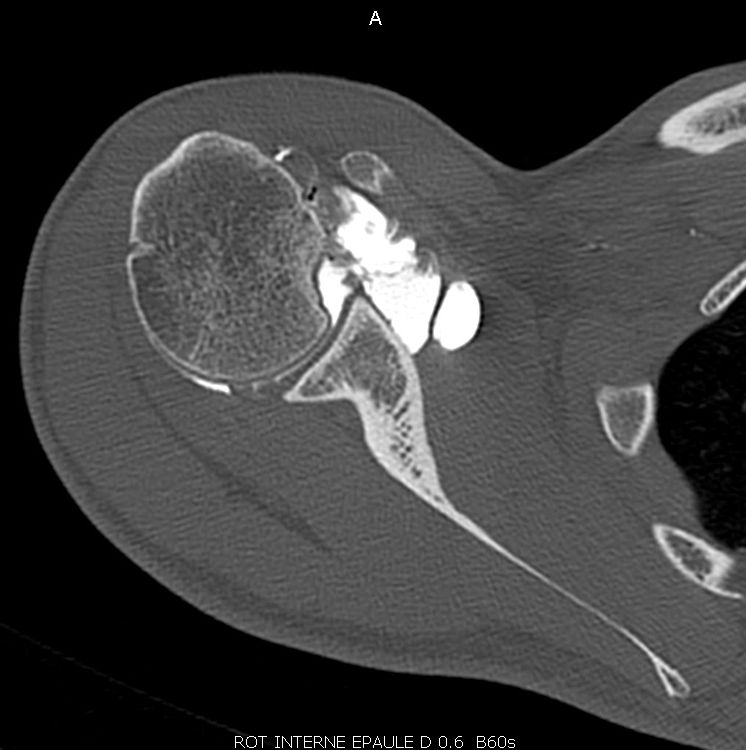

The clinical articles in this issue address four distinct domains. Knee revision surgery is examined through the application of 3D printed models, exploring their role in preoperative planning and intraoperative guidance. The diagnosis and therapeutic management of posterior shoulder dislocation are subsequently reviewed, followed by a focused analysis of trauma to the Lisfranc joint. The issue concludes with a critical appraisal of artificial intelligence in knee arthroplasty, considering its implications for surgical decision-making and outcome optimization.